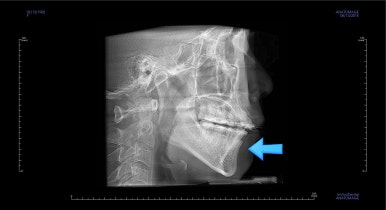

발치교정을 하였을 때, 흔히 나타나는 문제인데 앞니의 각도가 안으로 매우 굽어져 있습니다. 옥니라고 하며 발치를 한 공간을 너무 당겨 넣다보면 발생할 수 있습니다.

3번과 관련하여 더 큰 문제는 다음 사진에서 볼 수 있습니다.

안으로 굽었던 옥니의 각도가 역교정으로 다시 회복이 되었습니다.

가장 눈에 띄는 점은 윗니를 후방이동 시켰기 때문에 돌출감이 있었던 부분이 개선이 되었다는 점입니다.

앞니의 간격이 있으면 위쪽 입술은 나와보이고 아래쪽 입술은 말려 들어가는 등으로 입술선이 부자연스럽다거나 심미적으로 좋지 못하는데 이 부분이 좋아졌죠.

특히 옆모습에서 부터 턱끝까지 이르는 S라인이 살아나게 되면서 입술선이 훨씬 예뻐졌습니다.

아랫니의 위치를 크게 변화시키지 않고 거의 윗니만 조절했음에도 불구하고 전체적으로 좋아졌죠.